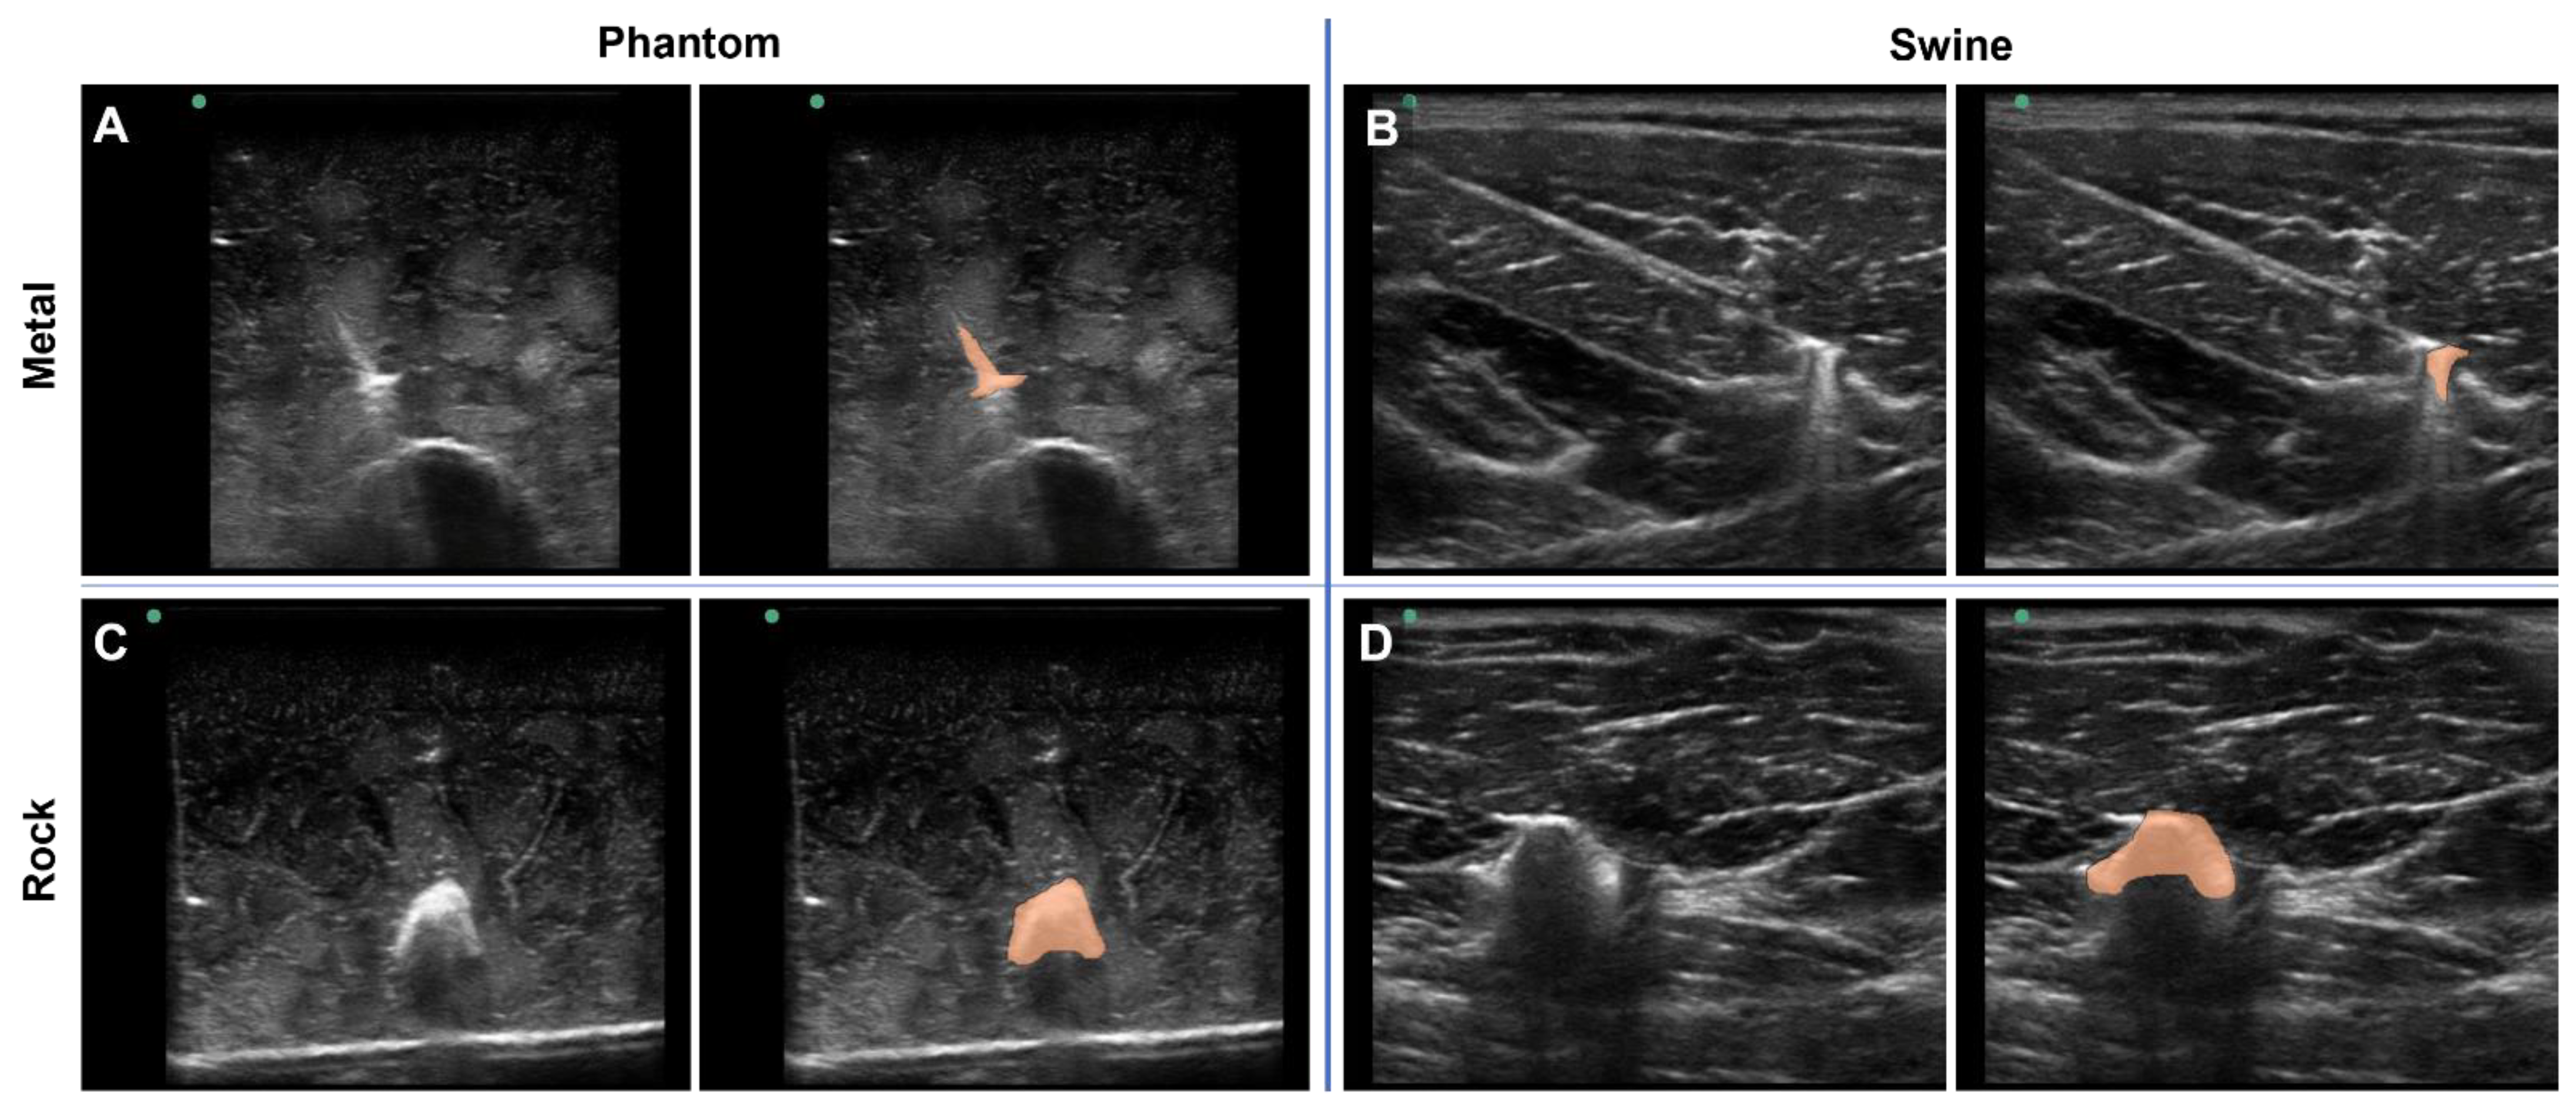

3.3. Phantom and Swine Training Datasets for ShrapML

3.2. Application for Automated Shrapnel Detection